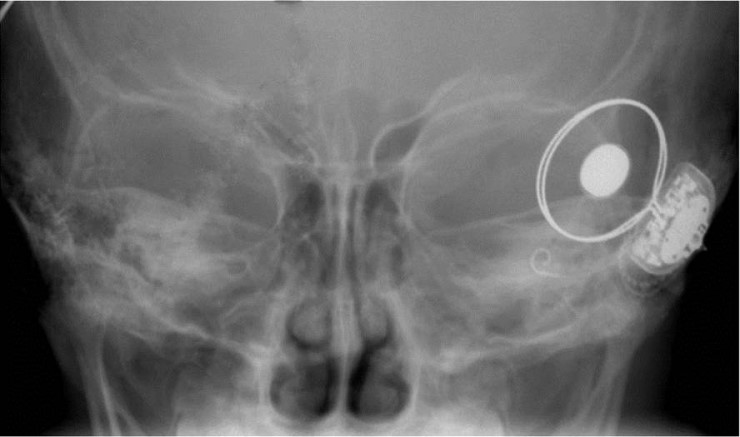

인공와우는 일종의 인공 달팽이관으로, 소리대신 소리 자극화된 전기신호로 청신경을 자극함으로써 뇌에서 소리를 인지하도록 하는 청각재활기기다. 인공와우 이식술은 선천적 장애나 후천적 난청으로 정상 청력을 상실한 환자에게 달팽이관을 대신할 인공와우를 이식하여 청력 기능을 회복하도록 하는 수술.

달팽이관의 신경세포가 손상되어 보청기로도 효과를 보지 못하는 환자들에게 시도하게 된다. 수술 시간은 두 시간 정도이며, 약 4일간의 입원 후 재활 치료가 이어진다.

인공와우 이식술은 1988년 처음 국내 도입된 이래 현재까지 약 7,500건이 이루어졌다. 이중 장선오 교수가 집도한 것이 700건 이상이니 그가 국내 인공와우 분야에서 차지하고 있는 위상과 비중을 짐작할 수 있다. 현재 국내 인공와우 이식술이 세계적으로도 뒤떨어지지 않는 수준에 오르기까지는 장선오 교수가 기여한 바도 크다.